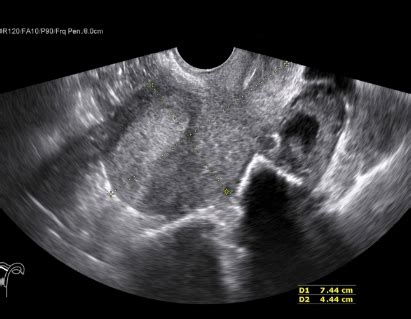

An ultrasound scanner , at its core, is a medical imaging device that uses high-frequency sound waves to create real-time images of the inside of your body. Unlike X-rays, which use radiation, ultrasound is generally considered a safe and non-invasive procedure. The process is pretty straightforward: a handheld device called a transducer emits sound waves that bounce off internal structures. These echoes are then captured by the transducer and processed by the scanner to generate images on a monitor. Think of it like sonar, but for the human body!

The magic of ultrasound scanners lies in their ability to differentiate between various tissues and fluids based on how they reflect sound waves. Denser tissues, like bone, reflect more sound waves than softer tissues, like muscles. Fluids, like blood or amniotic fluid, transmit sound waves more easily. This difference in reflection and transmission allows doctors to visualize organs, blood vessels, and even developing babies in the womb with remarkable clarity. The images produced, known as sonograms, provide valuable diagnostic information. Real-time imaging allows doctors to observe movement, such as the beating of a heart or the flow of blood through vessels. All of this is done without any incisions or exposure to radiation, making ultrasound a safe and versatile tool. It’s no wonder that ultrasound scanners are used in so many different medical fields, including obstetrics, cardiology, and radiology. They provide invaluable insights that help doctors diagnose conditions early and monitor the effectiveness of treatments.